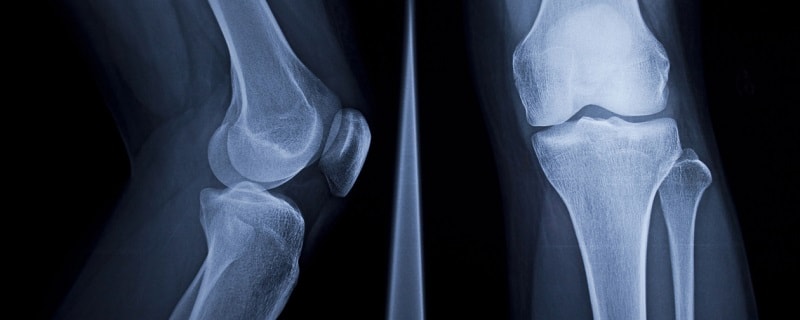

La maladie ne se manifeste qu’à un stade assez avancé, sous la forme de douleurs osseuses. Le diagnostic est alors réalisé au moyen d’examens radiographiques et d’une scintigraphie osseuse.

radio des os